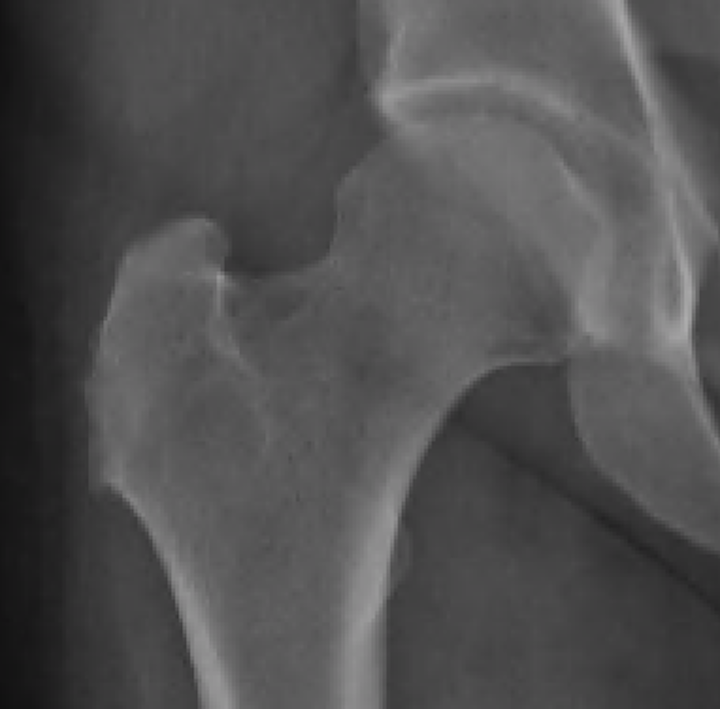

Figure 3 from Abductor Tendon Tears of the Hip Evaluation and